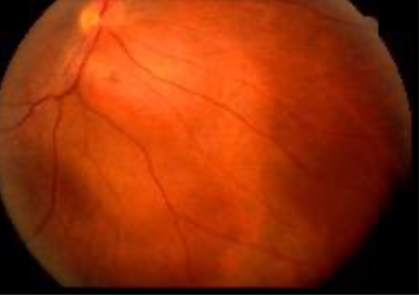

retinoblastoma

retinoblastoma

retinoblastoma